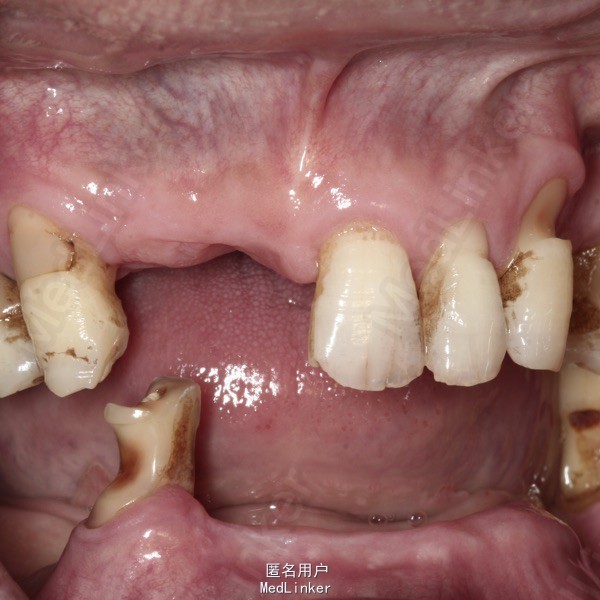

查体 辅查

上颌多颗前后牙缺失,下颌仅余留37和44。

诊断 处理

考虑下颌固位不佳,拟根管治疗44后磁性附着体修复下颌